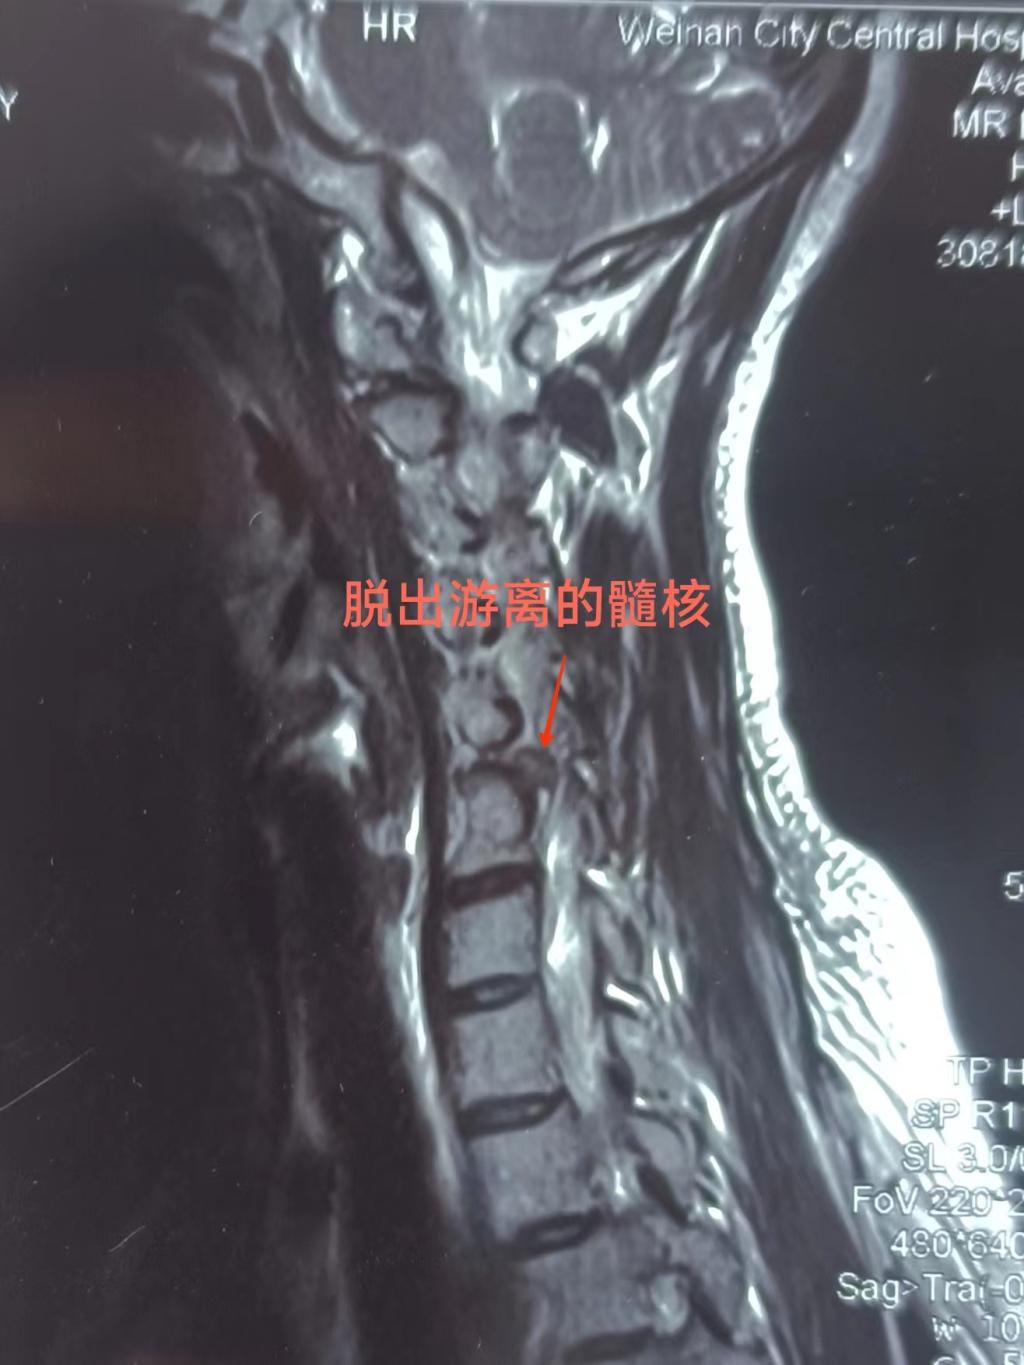

患者女性,43岁,入院时右上肢抽痛、麻木1周,行颈椎MR提示:颈4/5、5/6椎间盘突出,颈2.3后纵韧带骨化,颈椎曲度反弓。患者右肩部、右上肢抽痛明显,不能平卧,夜不能寐,痛苦万分。

入院后骨一科主任程福宏,副主任医师葛大明经查体,阅读影像学资料,确定病灶为颈5/6椎间盘。科室讨论认为:传统开放手术,需要多节段颈椎间融合内固定,手术创伤较大,术后恢复时间长,颈椎活动度后期有一定影响。考虑患者年轻,依照快速康复(ERAS)理念,准备微创在椎间孔镜下行后路颈5/6椎间盘摘除术。

经过充分术前沟通、准备,7月11日早晨进行手术,历时1个半小时,顺利结束。术中见颈5/6椎间盘右后侧突出,髓核游离,压迫颈6右侧神经根,取出髓核后,神经根完全松解。